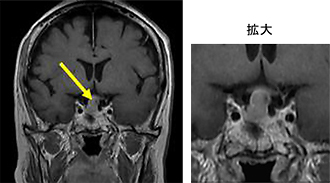

ラトケ嚢胞

ラトケ嚢胞とは

ラトケ嚢胞とは脳下垂体にできる袋状のできものです。この下垂体には様々な腫瘍が発生することがあります。かたまりとしてできるものと袋状になってできるものがあり、ラトケ嚢胞は袋状のできものの代表です。

ラトケ嚢胞とは脳下垂体に生じた粘液を含んだ嚢胞です。